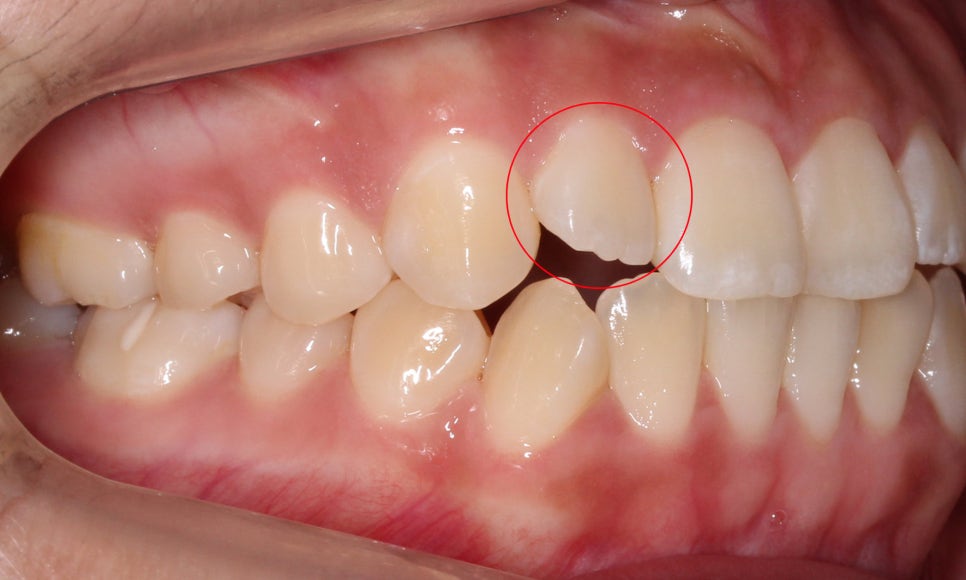

이렇게 환자분의 작은앞니(측절치)처럼

치아 끝이 울퉁불퉁하게 남아 있는 모습을

확인할 수 있는데요,

일반적인 경우 마멜론(톱니치아)은

시간이 지나면서 치아 끝이 마모되어

사라지게 됩니다.

그러나 환자분처럼 치아의

교합 상태가 좋지 않거나

왜소치로 인해 치아 끝이

마모되지 않는 경우

성인이 된 이후에도

마멜론이 남아있기도 합니다!

작은앞니(측절치)의 길이가

짧아 아랫니에 닿지 않는 모습입니다.

환자분의 Case는 왜소치로 인한

마멜론으로 볼 수 있겠죠?

반대쪽 측절치 역시

길이가 짧아서 치아 끝이

거의 마모되지 않은 모습입니다~